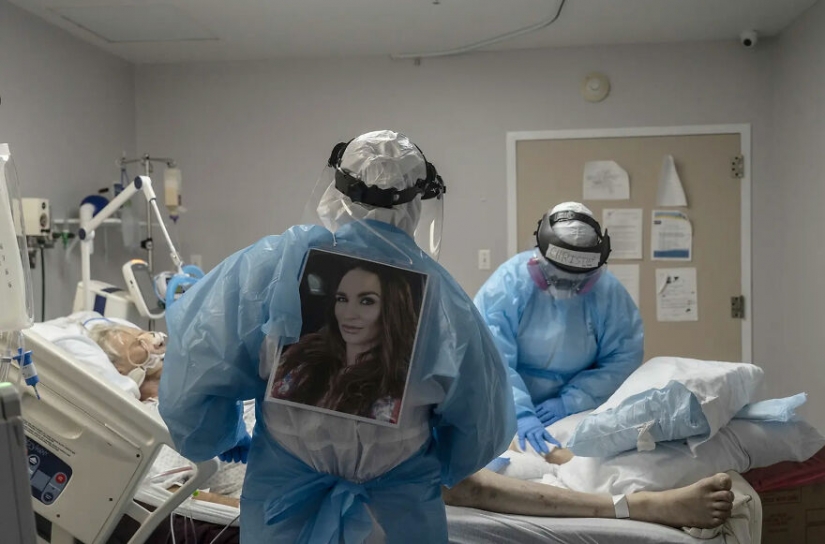

By Vika https://pictolic.com/article/8-photos-showing-the-reality-of-covid-19-in-hospitals.htmlFor many of us isolated in our homes, the battle on the front lines against Covid-19 remains a mystery. We do not know about the energy and sacrifice that the medical staff put into the fight against the pandemic, as well as all the suffering they cause to the sick.

However, Go Nakamura is here to give us a better understanding of the situation. The Houston-based photojournalist who moved to Texas just over a year ago has visited United Memorial Medical Center more than 20 times since May, documenting everything that happens in the COVID ward.

Hopefully, these photos will raise our collective sense of responsibility and remind us to do everything in our power to stay safe.

8. Medical staff treats a patient in the Covid-19 intensive care unit in Houston.